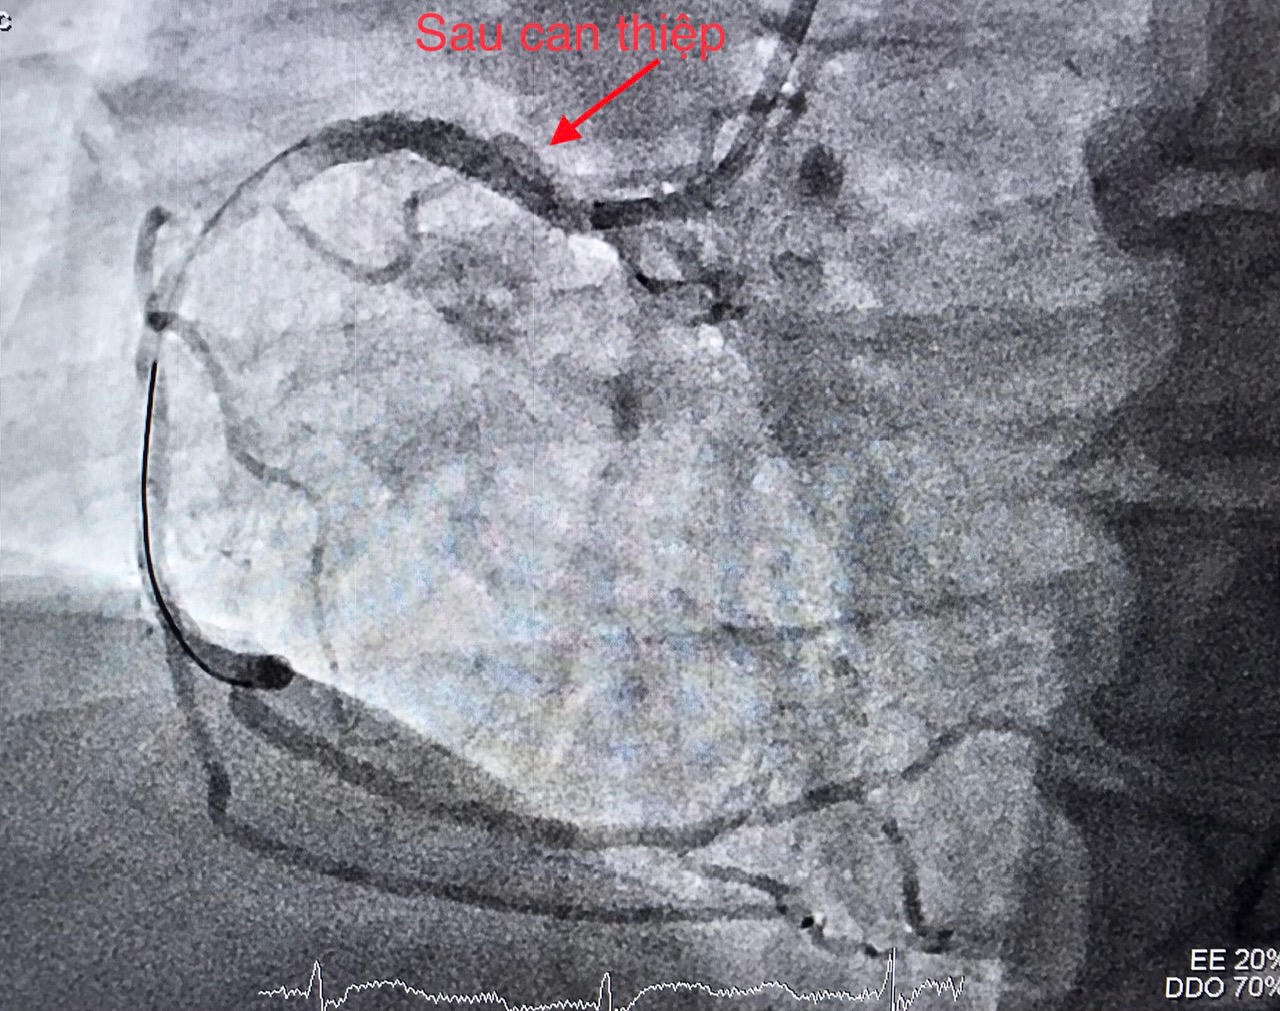

Các bác sĩ BVĐK TW Cần Thơ tiến hành hội chẩn với ê-kíp trực cấp cứu tim mạch can thiệp, sau đó chỉ định can thiệp mạch vành cấp cứu bệnh nhân.

Hình ảnh trên DSA mạch vành bị tắc trước can thiệp |

Thời điểm chuẩn bị đặt ống thông để can thiệp mạch vành, bệnh nhân liệt nửa người bên trái và nói đớ. Nhận định đây là một trường hợp hiếm gặp phối hợp giữa nhồi máu cơ tim cấp (do tắc động mạch vành) và nhồi máu não cấp (do tắc một mạch máu ở não), ê-kíp can thiệp mạch máu não lập tức được báo động để cùng phối hợp điều trị cho bệnh nhân. Kết quả CTscan não đúng như chẩn đoán.

Ê-kíp can thiệp tim mạch trong thời gian khoảng 40 phút đã hoàn tất nong động mạch vành bị tắc và tiến hành đặt giá đỡ (stent), giúp tái lập dòng máu nuôi tim. Ngay sau đó ê-kíp can thiệp mạch não chụp kiểm tra phát hiện tắc động mạch não giữa bên phải; thủ thuật lấy huyết khối tái thông mạch máu bị tắc với thời gian 20 phút.